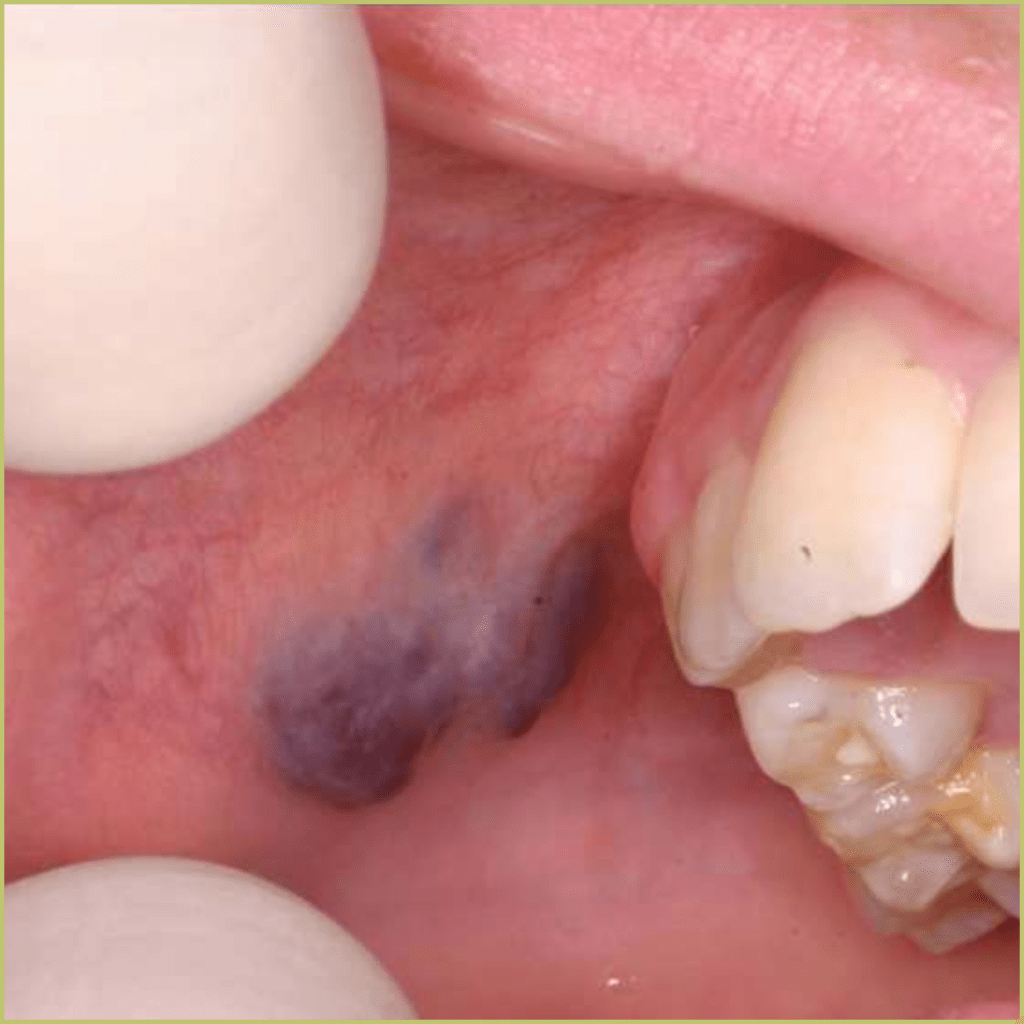

KAPOSI'S SARCOMA

Kaposi’s Sarcoma (KS) gained public attention as an AIDS-defining malignancy during the 80’s and 90’s. It can present in individuals without HIV infection (classic idiopathic KS), in sub-Saharan Africa patients (endemic KS) and in transplant recipients (iatrogenic KS). The etiologic agent of all forms of Kaposi’s Sarcoma is KS herpesvirus (KSHV or HHV-8). The common clinical presentation includes:

- Classic form – slow but pernicious growth over many years. Oral lesions are rare.

- Endemic form – rapid growth. Oral lesions are rare.

- AIDS-associated KS – affects oral keratinized mucosa and mucoperiosteal tissue.

- Blue-ish macules, may become nodular.

- Strong predilection for the hard palate, followed by gingiva, buccal mucosa, and tongue.

- Less commonly seen since the advent of better management of AIDS.

- Usually asymptomatic.

Diagnosis is based on the lesion history, clinical presentation and microscopic findings, which may include:

- Vascular proliferation in the dermis.

- Spindle cell proliferation.

- Formation of slit-like spaces that are not lined by endothelium.

- Extravascular red blood cells.

Your differential diagnosis should include:

- Hematoma or ecchymosis.

- Hemangioma.

- Malignant melanoma.

- Pyogenic granuloma.

- Amalgam tattoo.

Treatment options include:

- Radiation therapy.

- Intralesional therapy (interferon-α, vincristine, vinblastine, sclerosing agents).

- Chemotherapy (interferon-α, vincristine, vinblastine, bleomycin, daunorubicin).

The prognosis varies on the host’s immune status but is generally poor in patients who present with the AIDS-associated form.